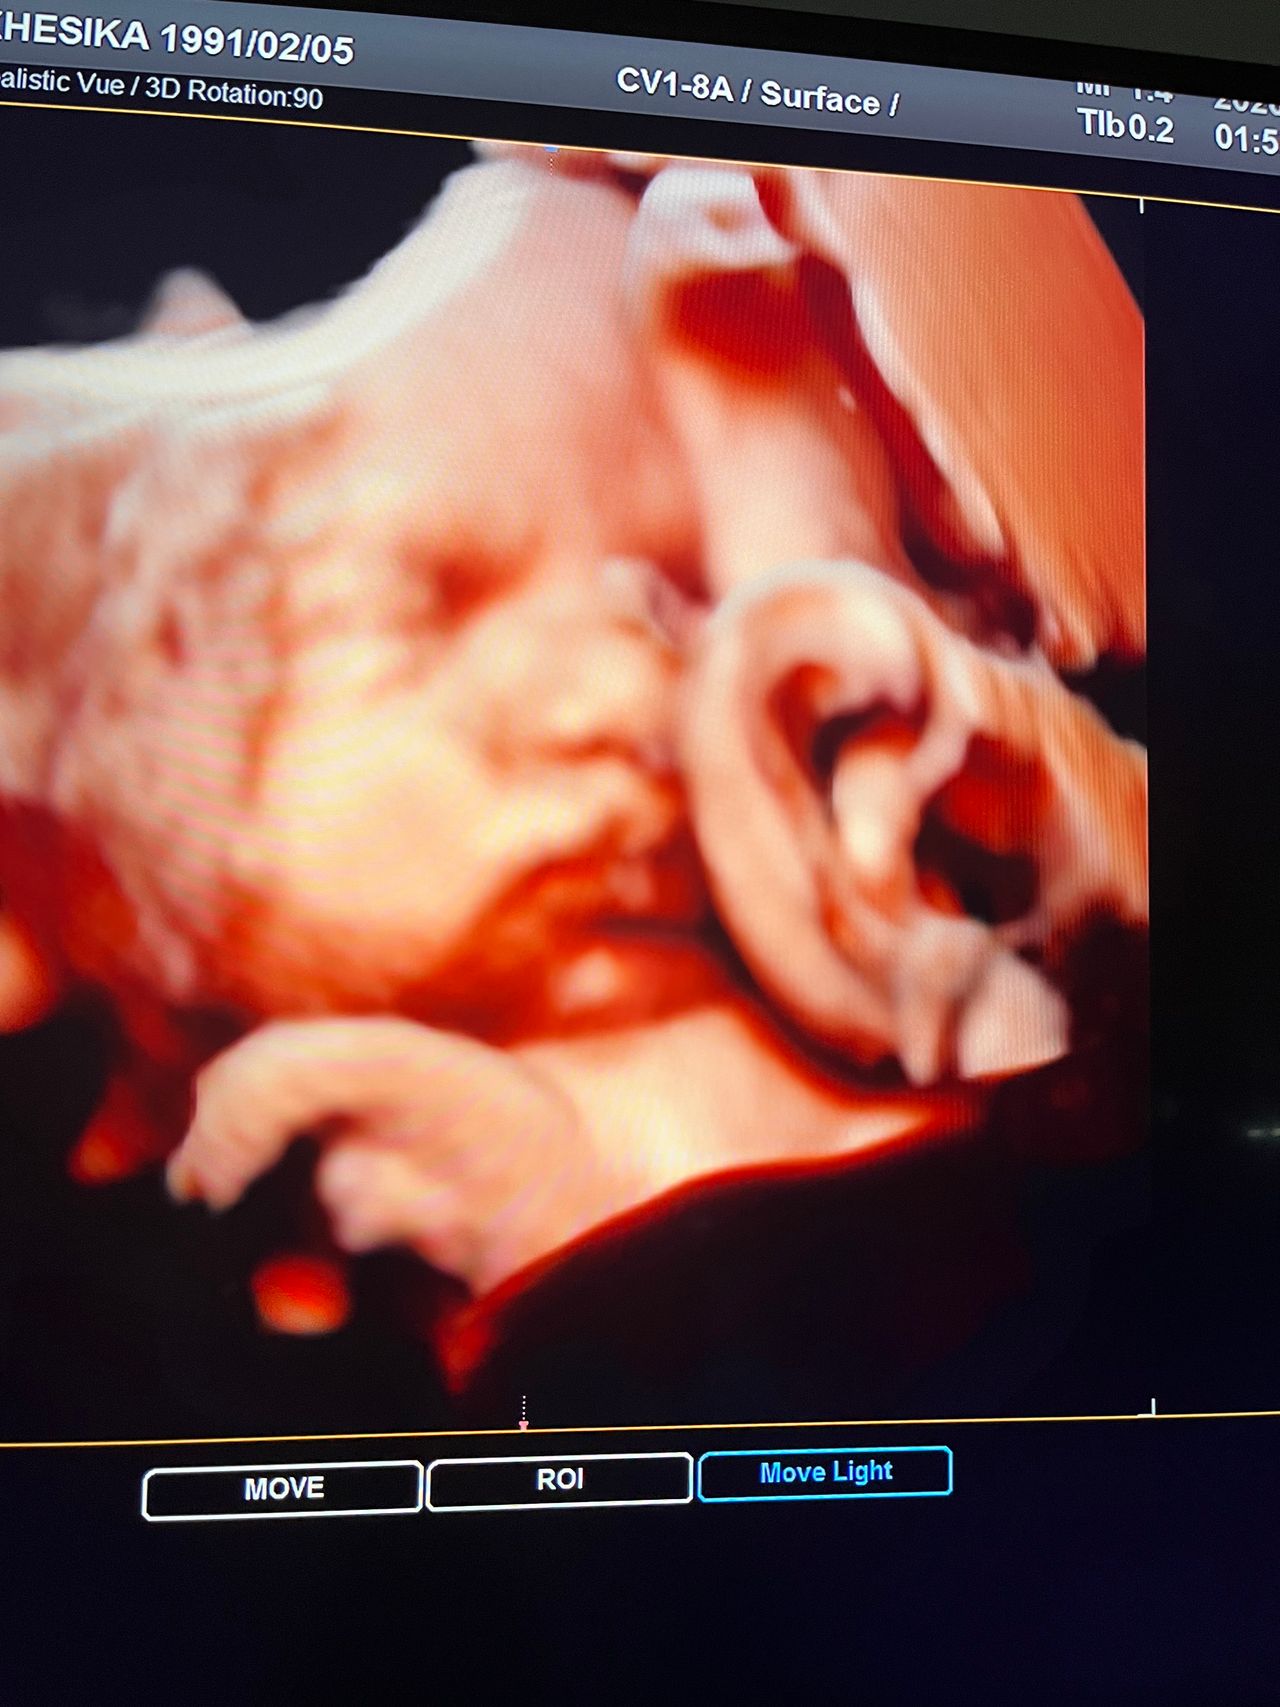

Attualmente lavoro come Dirigente medico nella SC di Ostetricia e Ginecologia dell'Ospedale Michele e Pietro Ferrero di Verduno, mi occupo prevalentemente di screening prenatale, ecografia ostetrica del I trimestre( misurazione translucenza nucale,NT), ecografia morfologica del II trimestre, ambulatorio pregresso taglio cesareo, ecografia ostetrica 3D. Seguo le gravidanze fisiologiche e quelle ad alto rischio , presto servizio in sala parto. Eseguo visite ginecologiche di I-II livello in regime ambulatoriale, counseling contraccettivo ed eventuale prescrizione pillola, inserimento spirale (IUD), dispositivo sottocutaneo (Nexplanon).

Foto e video